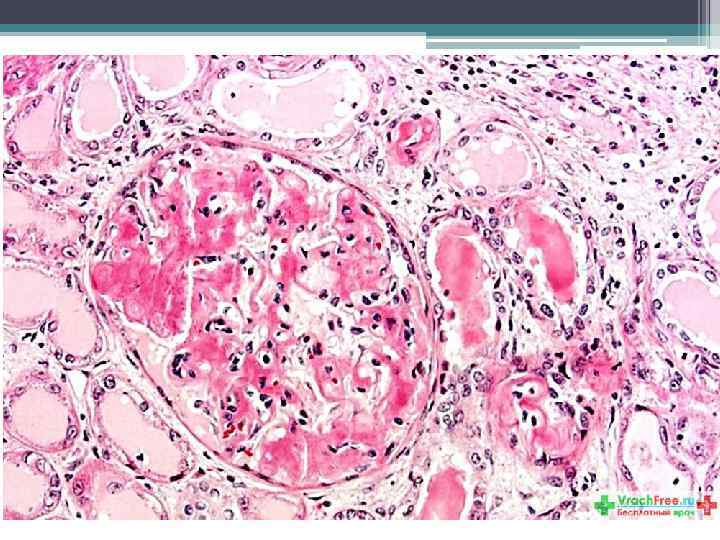

Трепанобиоптат костного мозга.